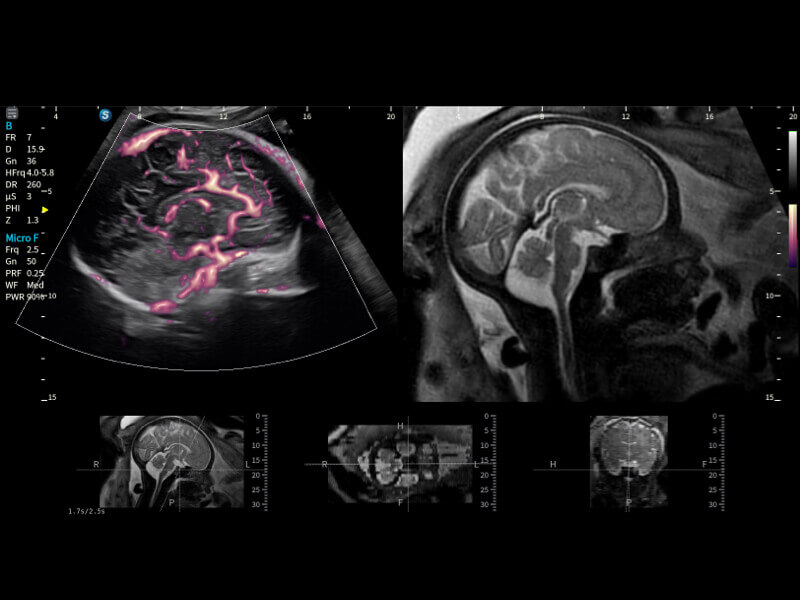

Fein abgestimmte hämodynamische Lösung

Eine Vielzahl hämodynamischer Diagnosetechniken ermöglicht eine effektive Blutflusssignaldetektion in verschiedenen Szenarien.

• Micro F

Micro F unterscheidet subtile Blutflusssignale effizient von überlagerter Gewebebewegung und ermöglicht eine erhöhte Empfindlichkeit sowie räumliche Auflösung in der hämodynamischen Darstellung.